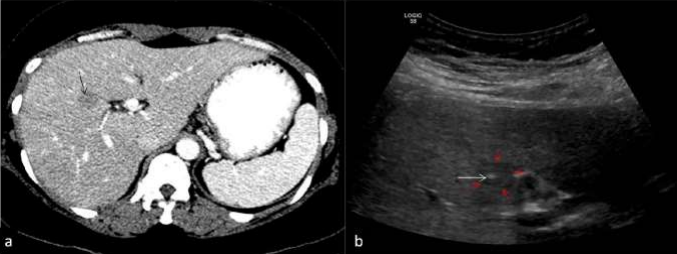

Figure 02: In this treated case of carcinoma rectum, surveillance CT scan reveals a 13 mm nodule in segment VII of liver (yellow arrow in a). USG guided FNAC was performed from this small liver lesion (as shown in b, yellow arrows). Entire course of the 15 cms 23G chiba needle (white arrows) is seen when the needle is parallel to the transducer. Tip of the needle is seen in mildly hyperechoic liver lesion in segment VIII (yellow arrows). Blue arrow shows hepatic vein. Cytology report suggestive of metastasis.

Figure 03: USG guided biopsy has been performed from the right lobe liver lesion in this suspected case of carcinoma gall bladder with liver metastasis. Almost entire needle (arrows) is seen in a with its tip in liver lesion (asterisk). Color doppler image shows vessels (in red and blue colors) on either sides of needle (arrow) which is carefully inserted avoiding the vessels.